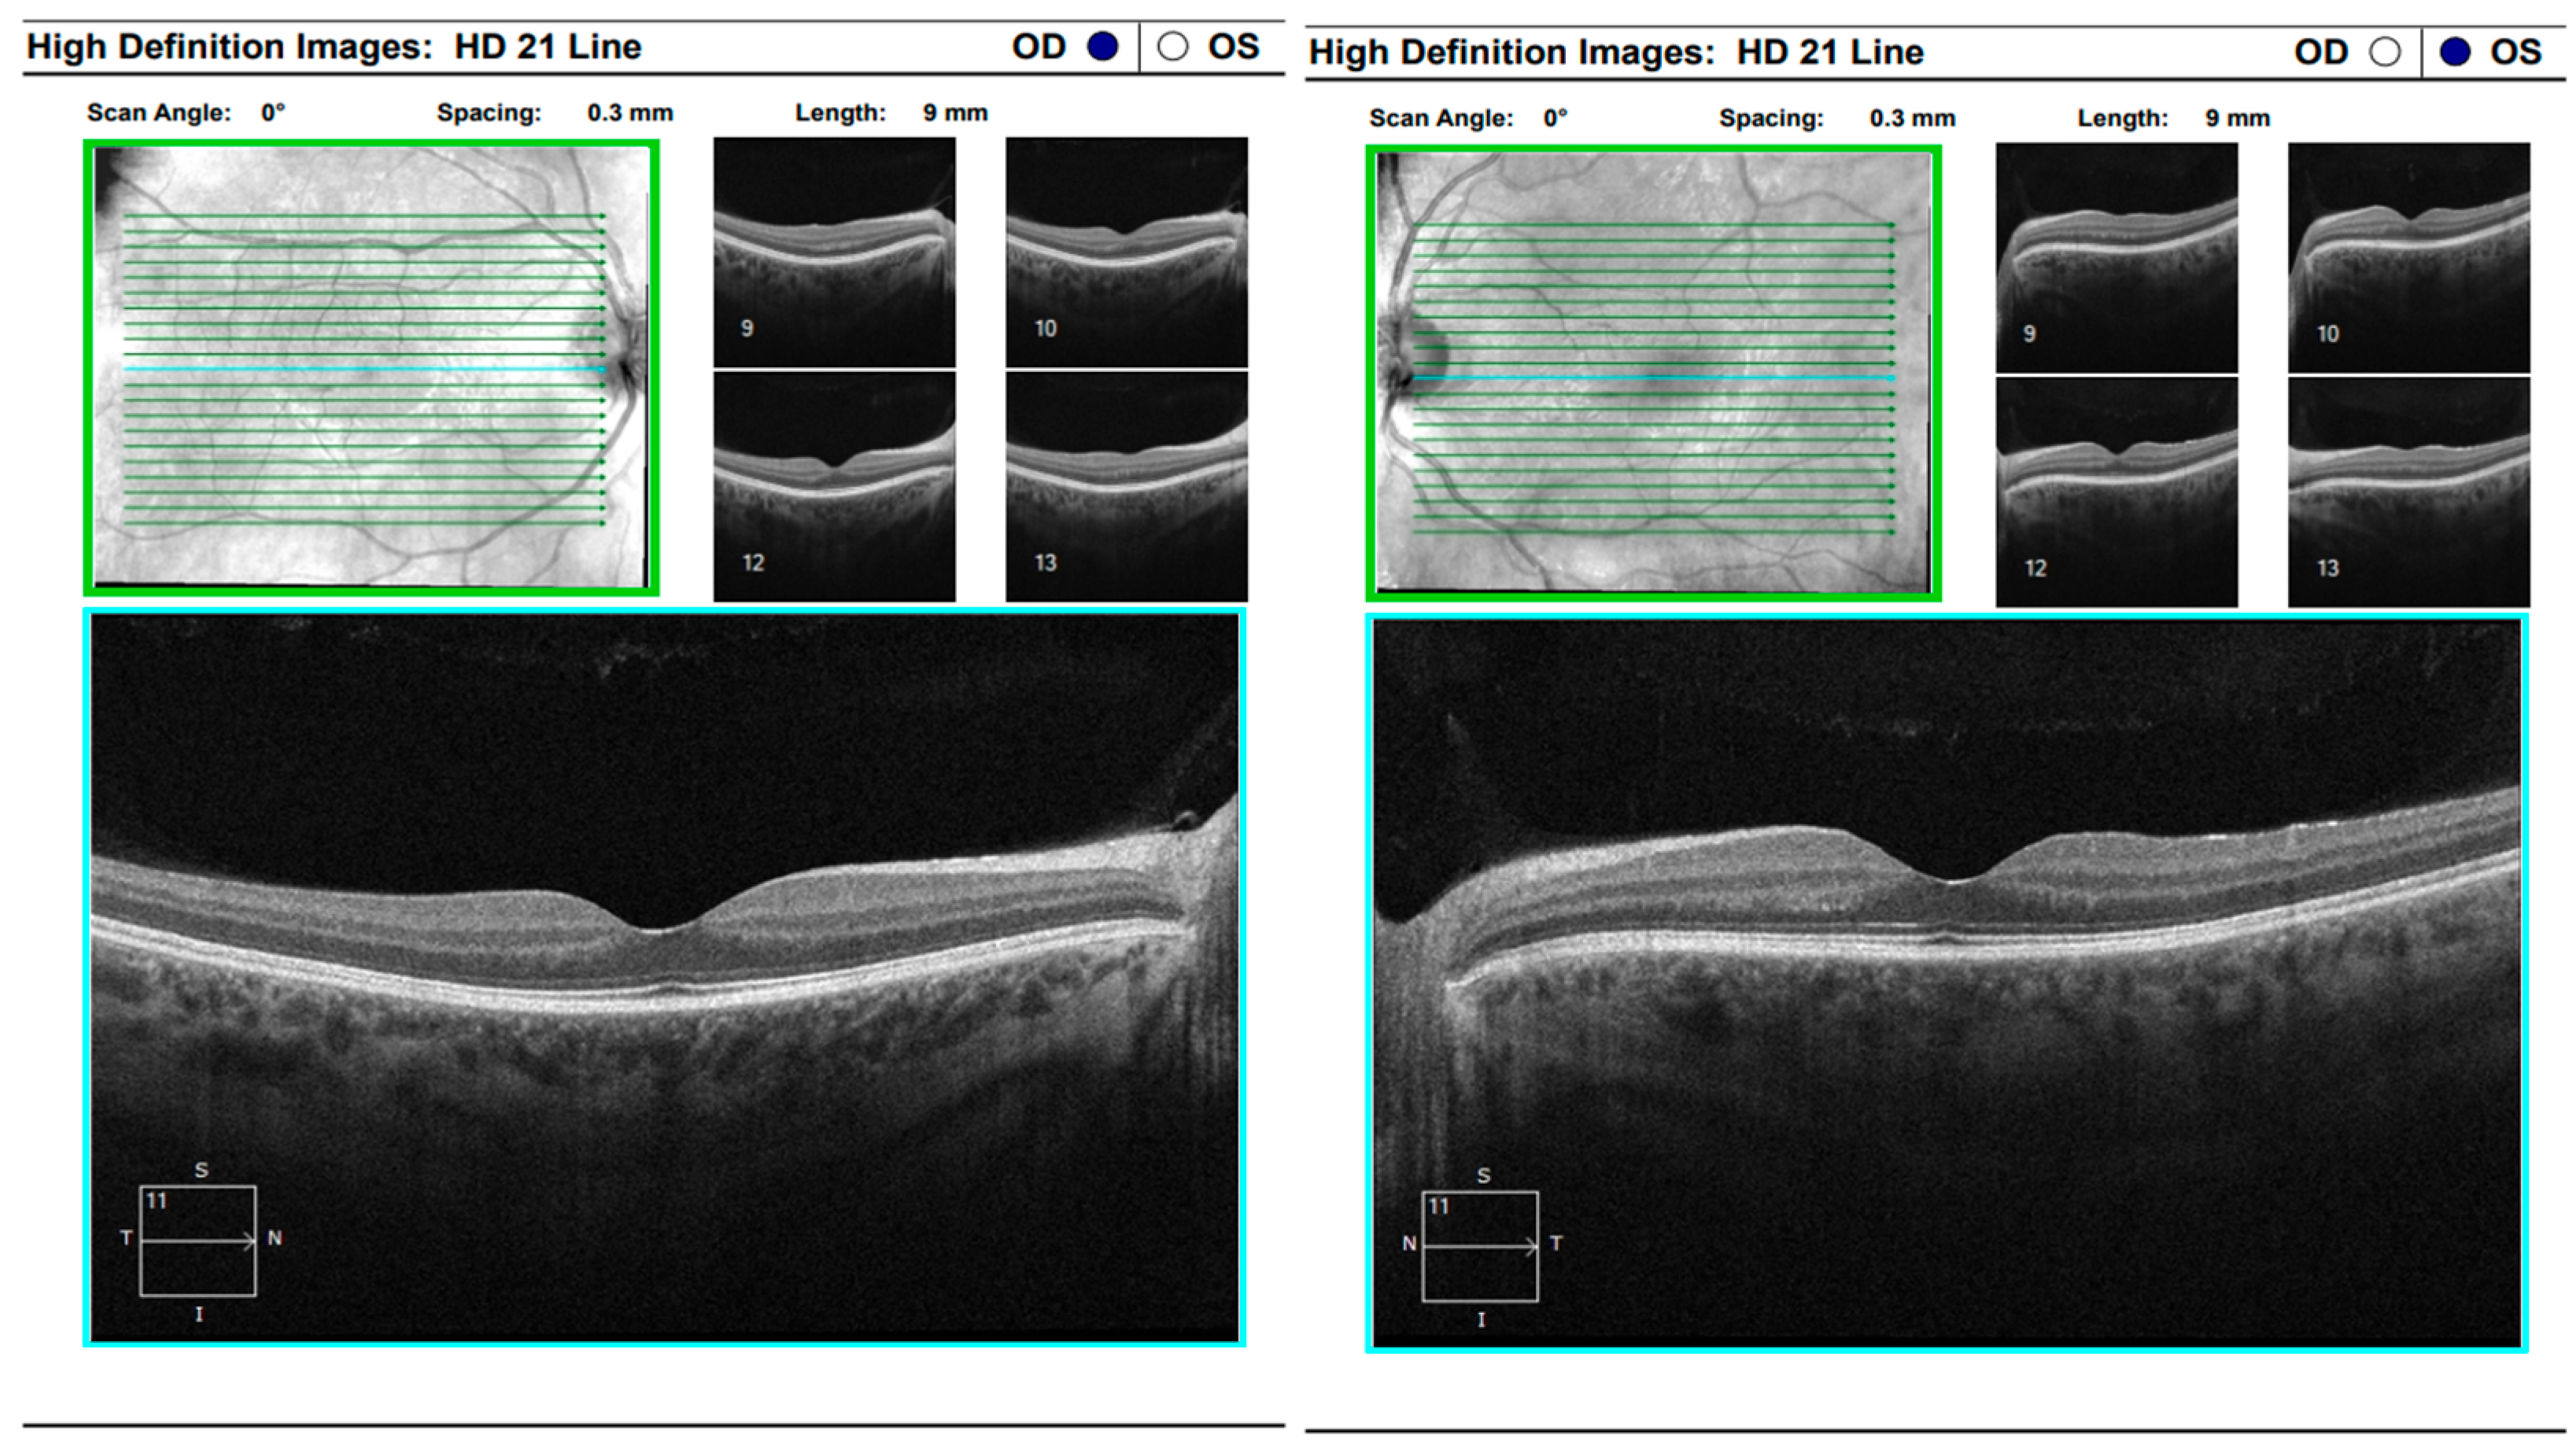

One year later, the patient returned to the Eye Hospital—Varna with complaints of pain, discomfort, and difficulty focusing in the left eye, accompanied by persistent headache. Visual acuity in the right eye remained 1.0, with no observable structural abnormalities. In contrast, visual acuity in the left eye had decreased to 0.7, with subjective metamorphopsia. Fundoscopic examination of the left eye revealed an exudative retinal detachment nasal to the macula, which was confirmed by optical coherence tomography. During the evaluation, the patient reported a history of hearing difficulties and presented documentation from an otorhinolaryngology consultation indicating idiopathic sensorineural hearing loss. OCT demonstrated paramacular edema with detachment of the pigment epithelium extending from the papilla to the nasal macula, consistent with chorioretinal inflammation in the left eye (Figure 16).

Comprehensive interdisciplinary evaluation of the clinical and imaging data supported a diagnosis of Vogt–Koyanagi–Harada (VKH) disease, prompting urgent hospitalization. Pulse therapy with intravenous Methylprednisolone was initiated, complemented by local parabulbar administration of Dexamethasone. The patient exhibited rapid improvement, with resolution of subjective symptoms, normalization of visual acuity in the left eye to 1.0, and marked reduction in papilledema. She was discharged with a prescription for oral Prednisolone to be continued for a minimum of six months. At nearly one year following the most recent hospitalization, the patient’s condition remains stable (Figure 17 and Figure 18).

Figure 16. Analysis protocol “HD 21 Line” of the left eye.

Figure 17. Analysis protocol “HD 21 Line” of the right and left eye.

Figure 18. Analysis protocol “Optis Disk Cube 200 × 200” on the right and left eye.